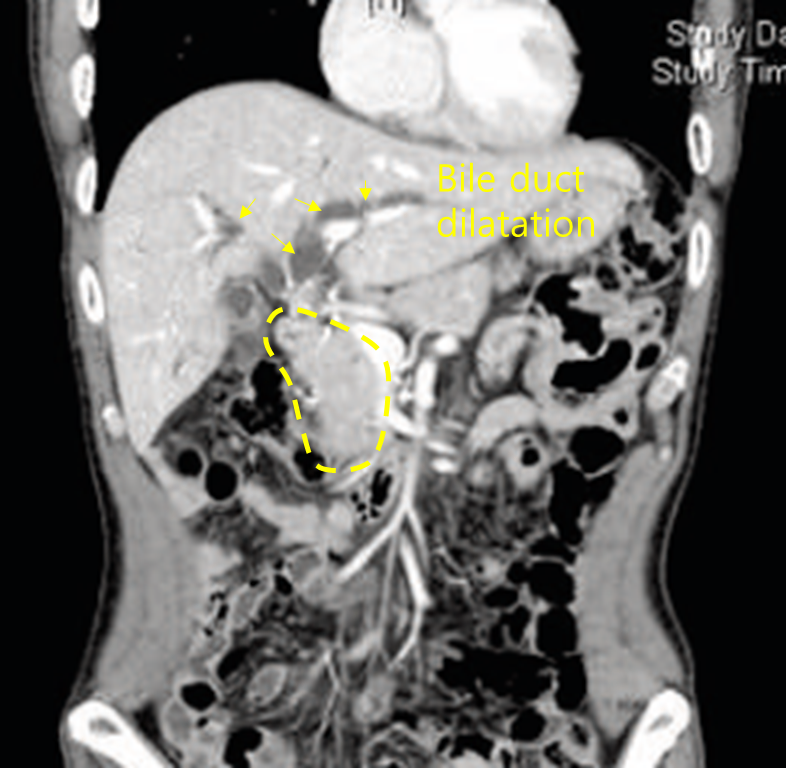

Img | CT: Mass invading CBD and possibly CHD, with IHD dilatation MRCP: IHD dilatation, without definite visible confluence of RHD and LHD |

• CT 및 MRCP상 intrahepatic bile duct가 dilatation되어 있으며, MRCP상 RHD와 LHD가 만나는 지점이 보이지 않으므로 CT상 확인되는 mass가 CHD를 침범했음을 알 수 있다. 즉, obstructive mass는 porta hepatis 주변에 있으며, 따라서 hilar cholangiocarcinoma의 가능성이 가장 높다.